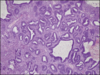

Benign prostatic hyperplasia - cause & Microscopy.

Cause- -prostatic levels of dihydrotestosterone (DHT) remain high with aging, even though peripheral levels of testosterone decrease due to high 5-alpha reductase activity.

Microscopy-

Most commonly affects the inner peri-urethral zone of the prostate. -variable proportions of stroma and glands hyperplasia.-hyperplastic glands are lined by two cell layers, an inner columnar layer and an outer layer composed of flattened basal cells.